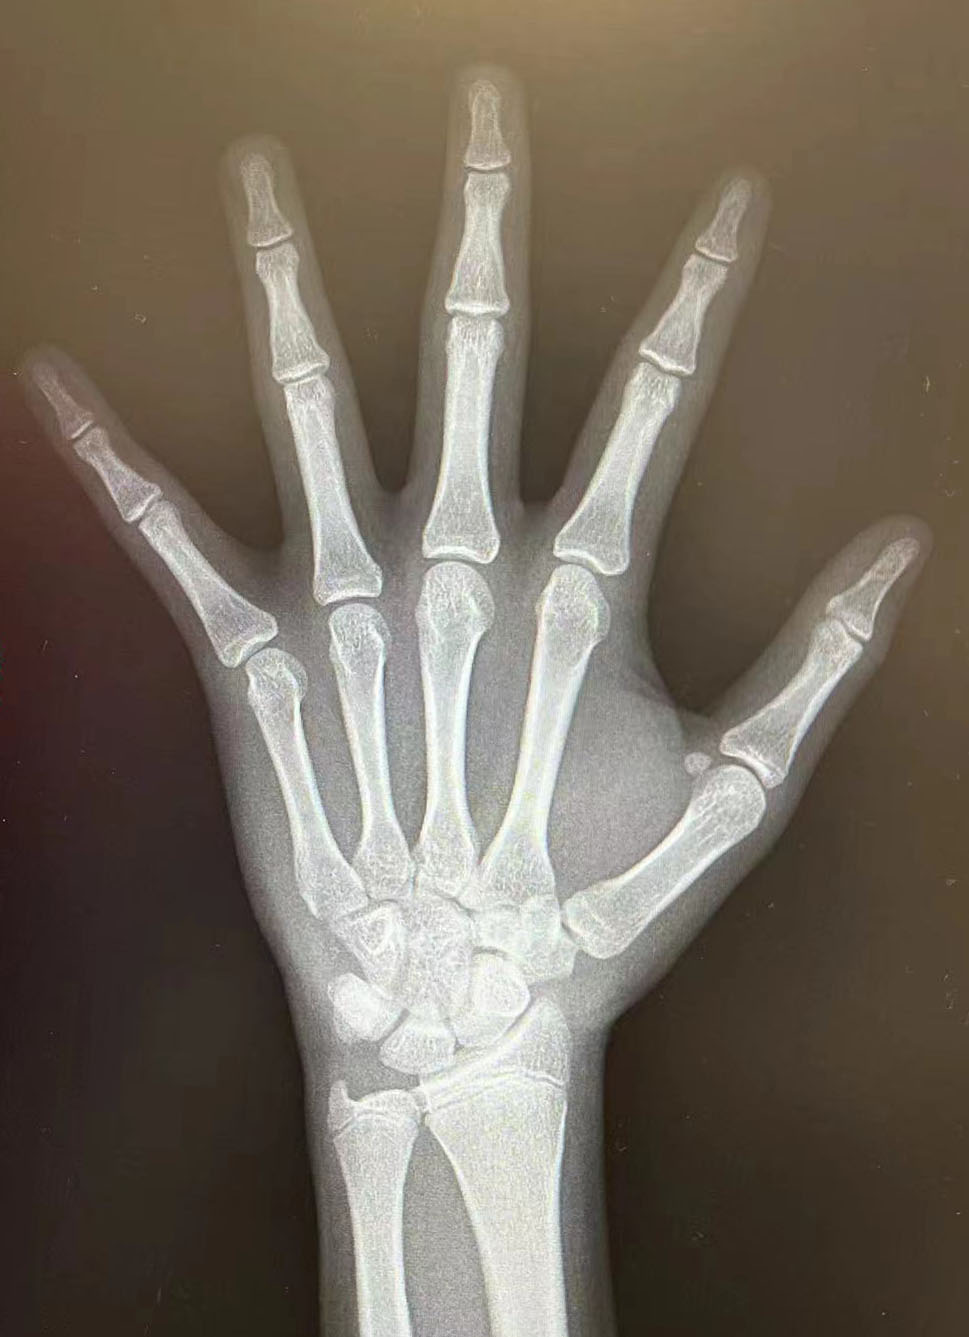

帮忙算一下骨龄,儿童医院算出15.1岁骨龄,把我吓到了

图片尺寸1290x1646